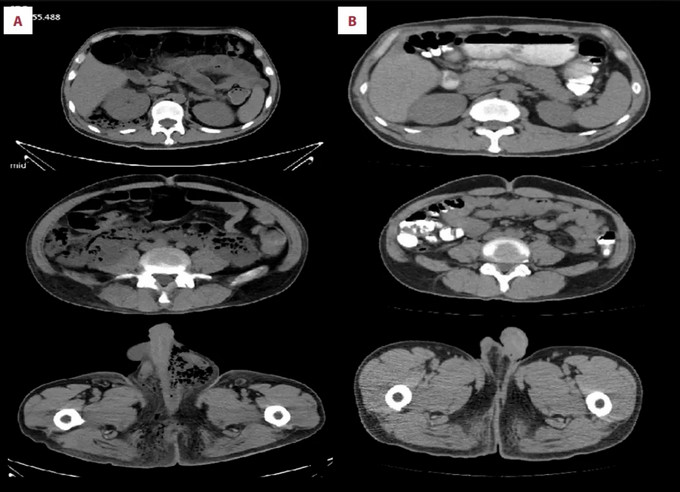

治疗前后影像对比:【A】为术前CT影像,【B】为术后1个月CT复查情况

文章分别围绕两例罕见肛周坏死性筋膜炎病例展开:其一为感染突破肛周区域,沿筋膜间隙延伸至腹膜后,形成大范围坏死灶(此类病例临床罕见,文献报道占比不足10%)。团队及时实施专科化清创与引流方案,术后结合专科创面护理与基础病管理,患者最终痊愈。其二为感染扩散至会阴部及大腿内侧,传统手术易导致肛周皮肤大面积缺损、功能受损。中心团队创新采用“皮肤保留清创术”,在彻底清除感染的同时守护肛周功能与外观,术后融入中医特色护理,患者创面顺利愈合,保护了肛门功能。